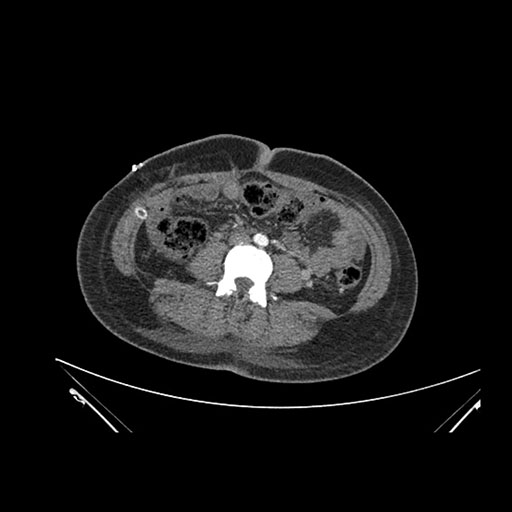

Axial Arterial

Axial Venous